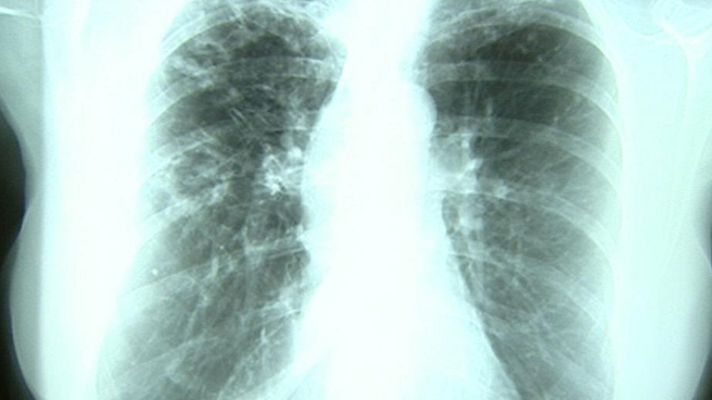

Hoy es el día Mundial de la Tuberculosis, una enfermedad contagiosa por vía aérea que afecta, sobre todo a los pulmones. En España, los emigrantes, seropositivos, diabéticos o fumadores son los grupos más sensibles. Un tercio de la población mundial está infectada.